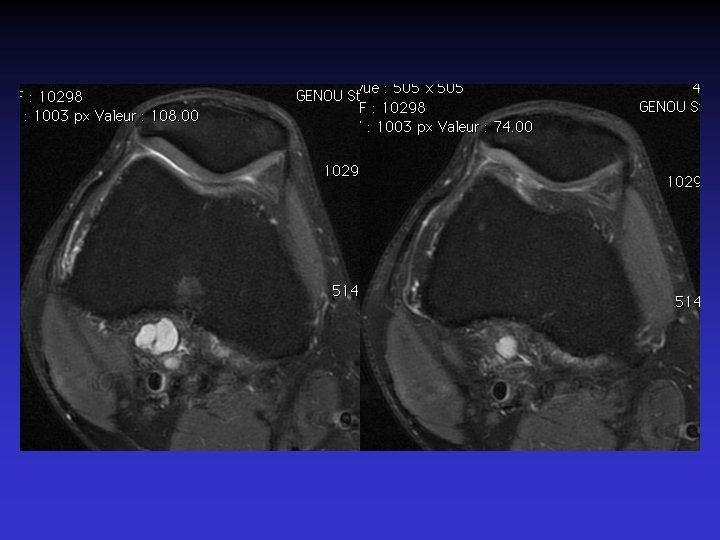

ATTEINTE BILATERALE • Non exceptionnelle • Concomitante ou décalée dans le temps

Mme S… 60 ANS DROIT

Mme S… 60 ANS GAUCHE